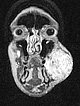

Axial, T2-weighted MRI at the level of the cheek shows the AVM to be relatively hyperintense with edema of the surrounding tissue and extension to the left mandible. In the rostral section some black flow voids are visible as a sign of arteries with fast flow within the AVM.